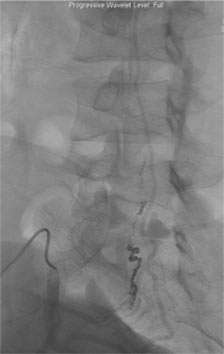

On the other hand, most dural or epidural AVFs are curable by surgery or catheter embolization. Our experience clearly shows “the sooner the treatment the better the outcome”. In our institution, minimally invasive catheter embolization was feasible in 75% of dural AVF cases. In the rest of 25% cases, surgical resection was performed. Both treatment methodologies result in a very high cure rate.

Figure 4: Catheter Embolization of a Spinal Dural AVF.